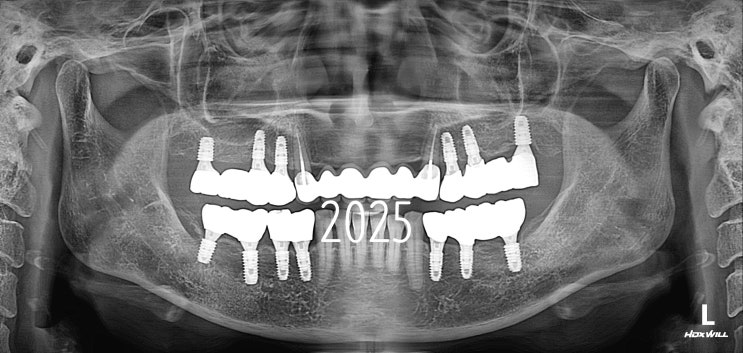

수원치과병원 라운드치과병원 10주년 "2015년 9월 처음 오신 김OO님"

개원 11주년을 맞이하는 라운드치과병원입니다. since 2014 라운드치과병원에서는 2024년에 이어서 2025년...